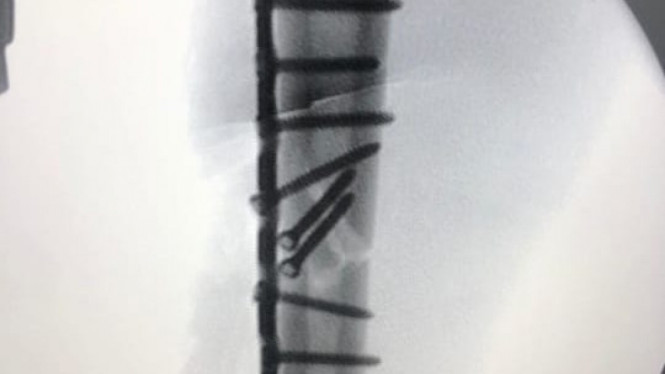

Pembalap berusia 27 tahun itu kerap menggunakan handsock atau deker tangan untuk menutupi bekas luka. Namun menariknya, Marquez mengunggah foto dan video yang memperlihatkan kondisi lengannya pada akun Instagram pribadi miliknya.

Dalam postingannya pembalap asal Spanyol ini memperlihatkan kondisi patah tulang yang dialami. Malahan Marquez membandingkan kondisi saat tulangnya terpisah sampai kemudian disatukan oleh pelat-pelat metal hasil operasi yang dilakukan.

Marquez memposting foto tersebut melalui akun instagramnya, Senin (27/7) hari ini. "Selamat pagi semuanya! Kita memulai minggu dengan energi besar. Tapi sebelum itu, selamat menikmati foto-foto dari pekan lalu," tulis Marquez pada caption foto.